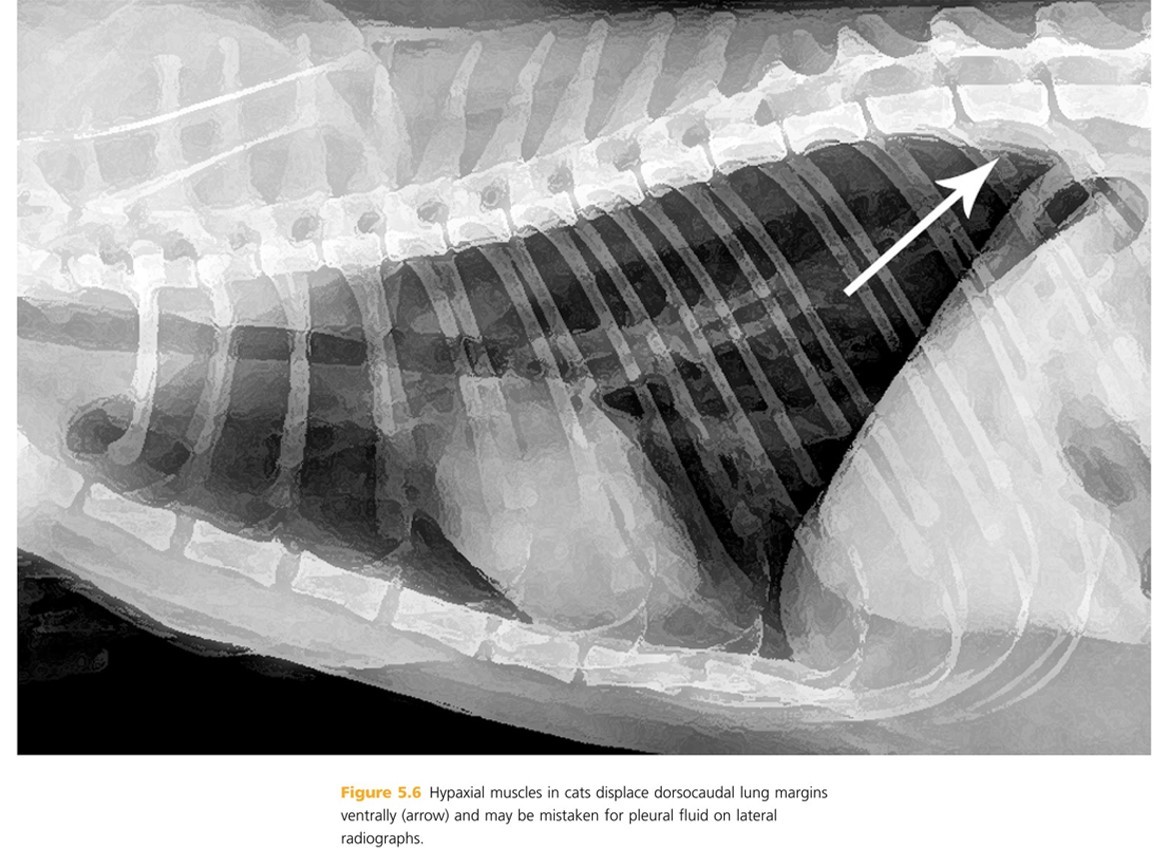

Hypaxial muscles in cats displace dorsocaudal lung margins ______ and may be mistaken for ____ ____ on radiographs.

pg. 280 ventrally, pleural fluid